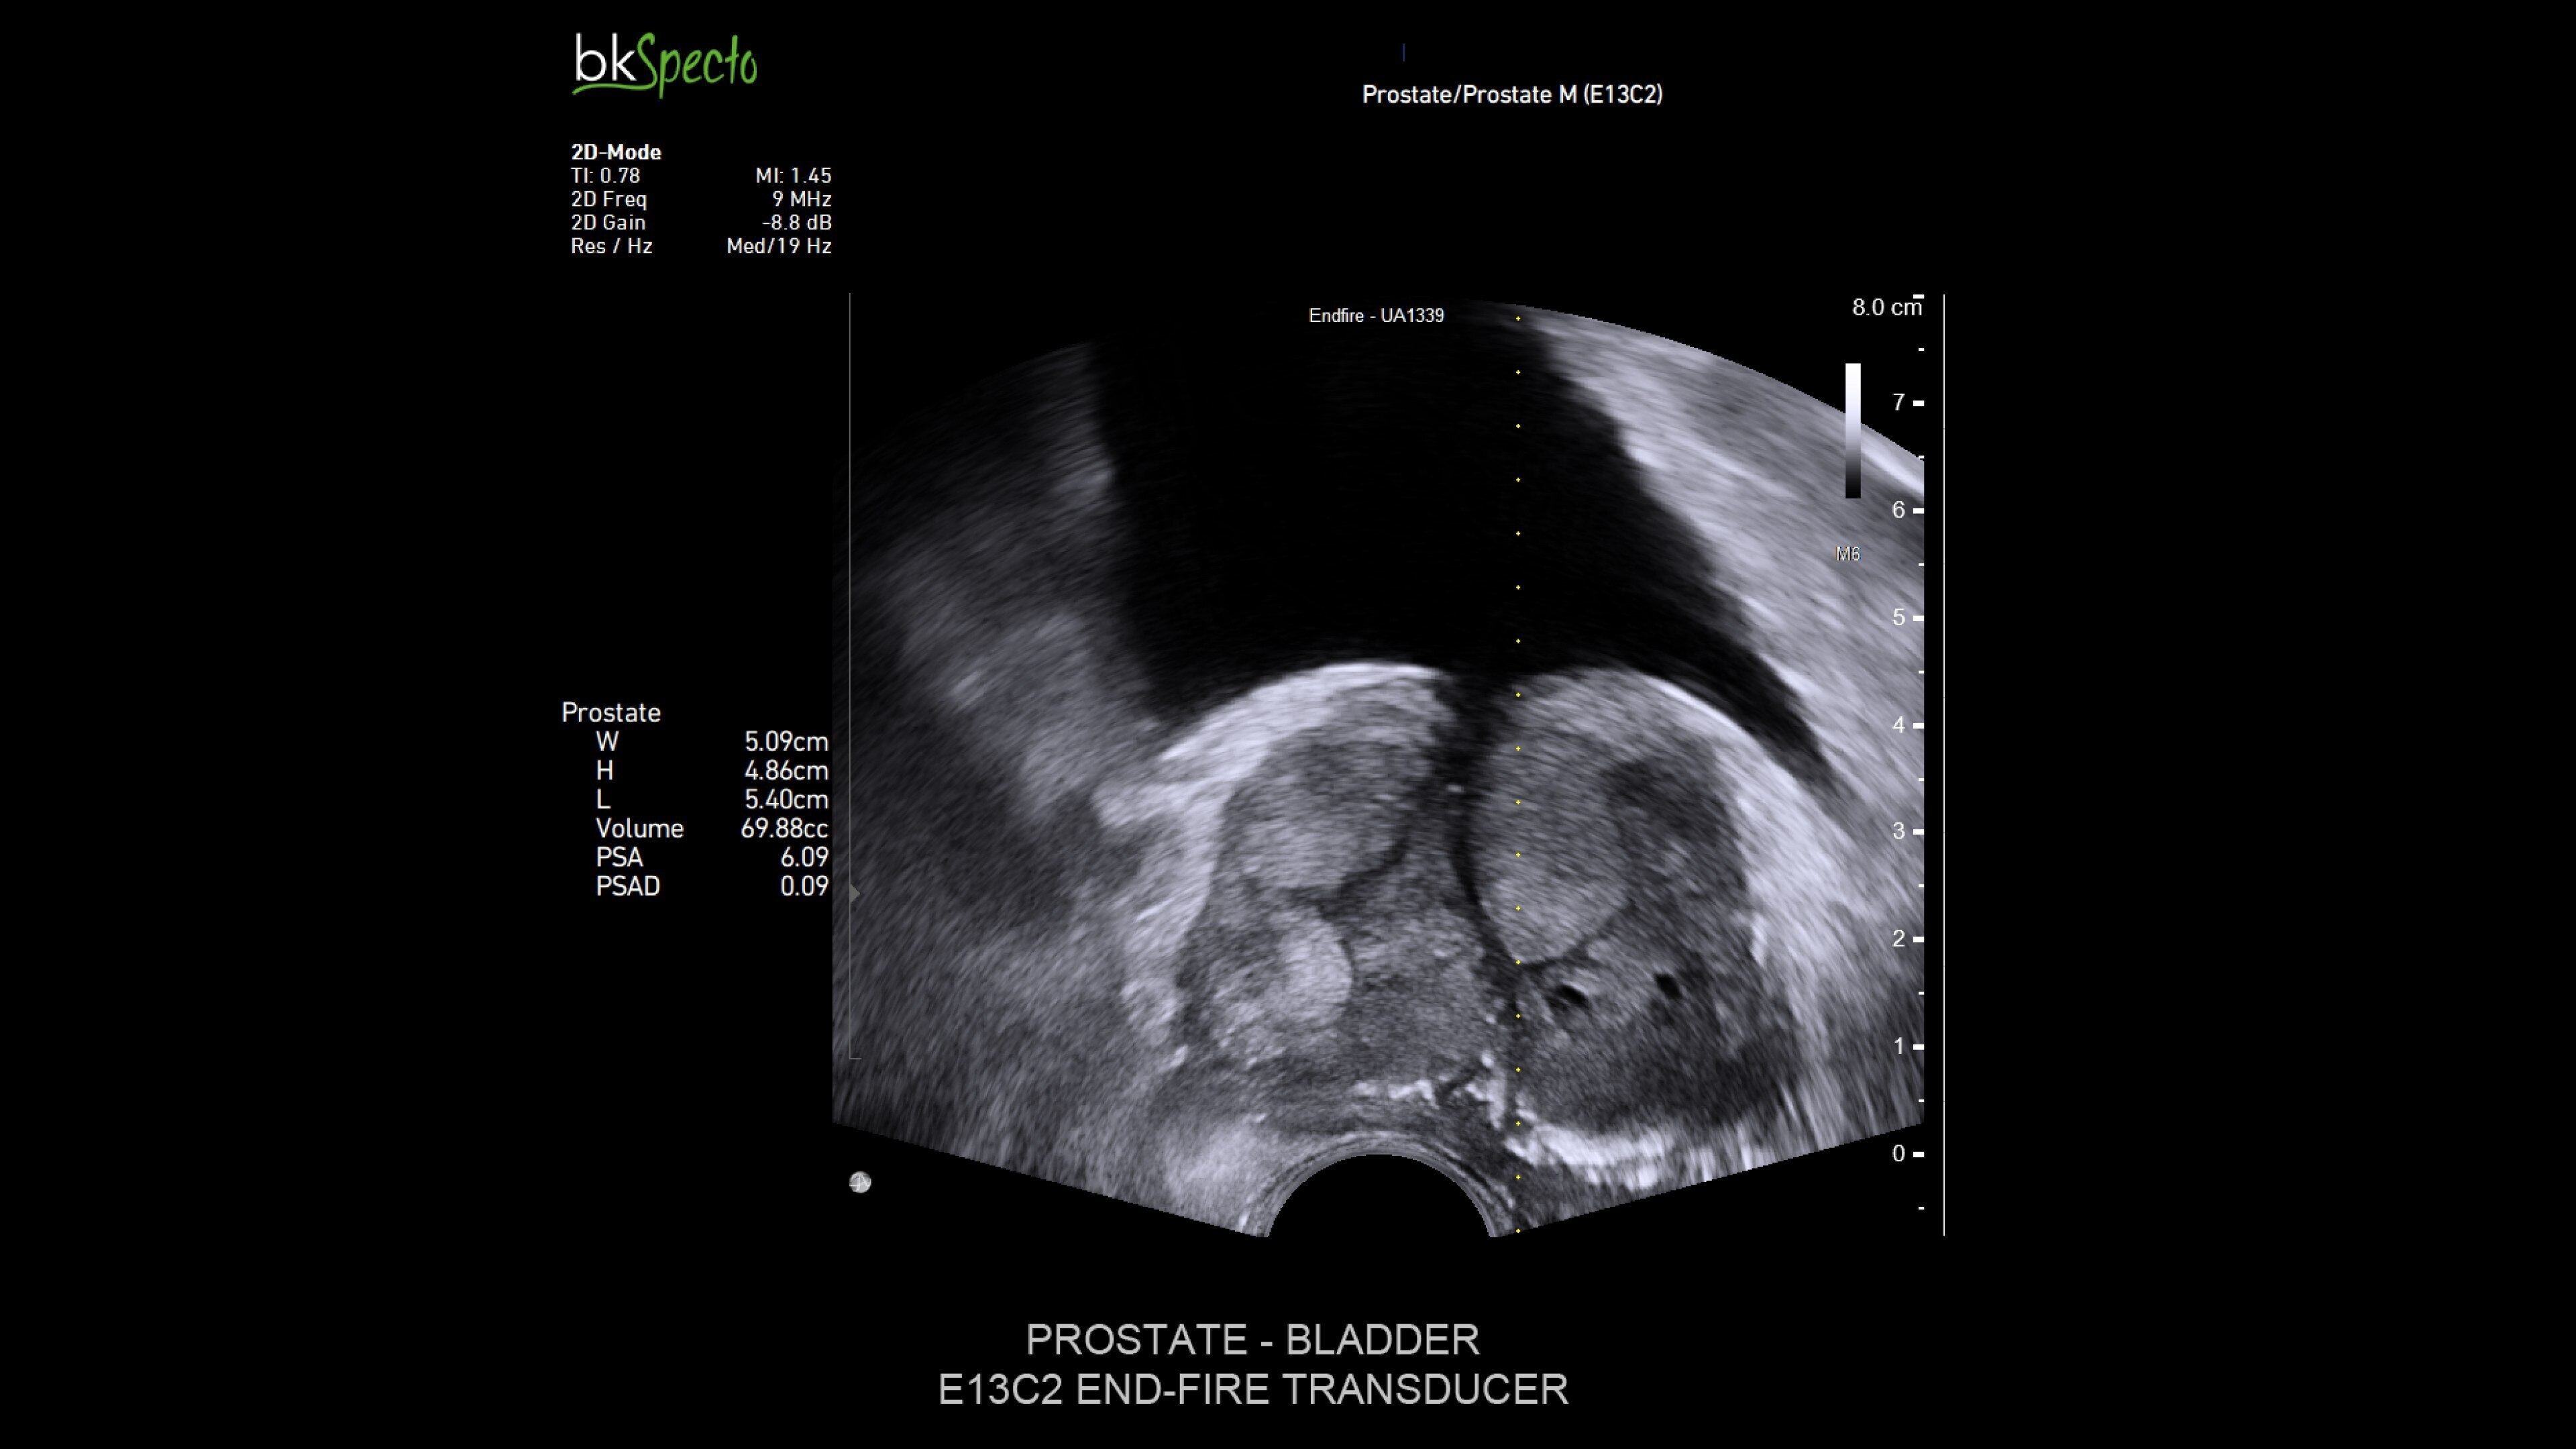

The bkActiv ultrasound system offers advanced imaging for urology, providing detailed visualization of the prostate, kidney, bladder, and pelvic floor (prostate imaging and biopsy, brachytherapy, cryotherapy). Its intuitive Tru-Sense™ touch interface and Smart Button™ technology allow for one-handed operation, ensuring full control during procedures. Confidently visualize and target regions for intervention with high-resolution detail and enhanced penetration when it matters most–during the procedure.1